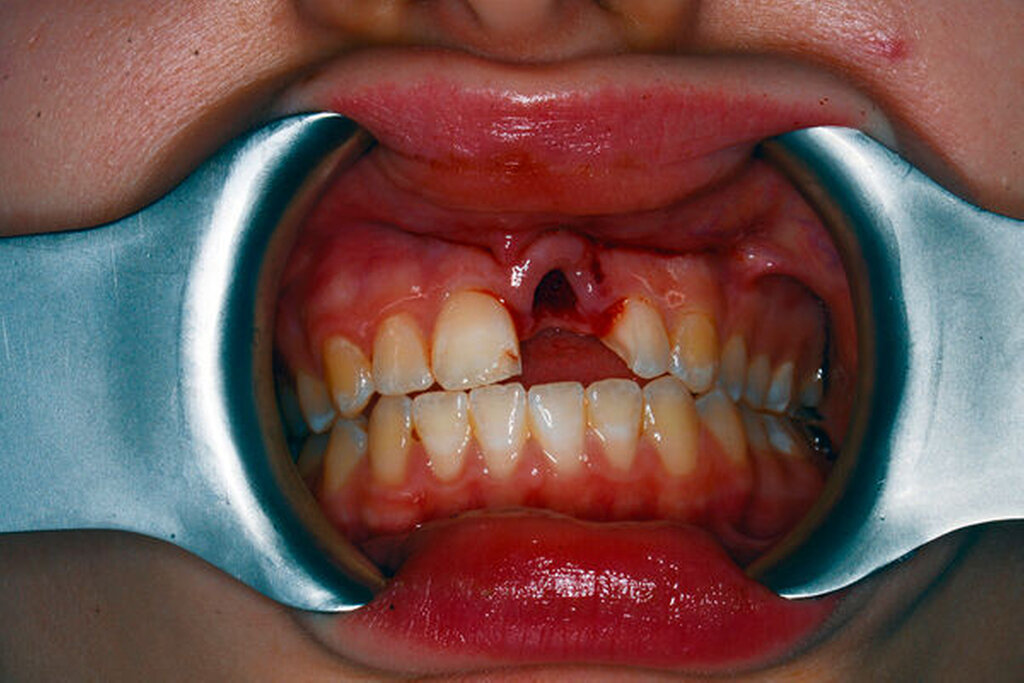

Symptomatische irreversible Pulpitis (Abbildung 3)